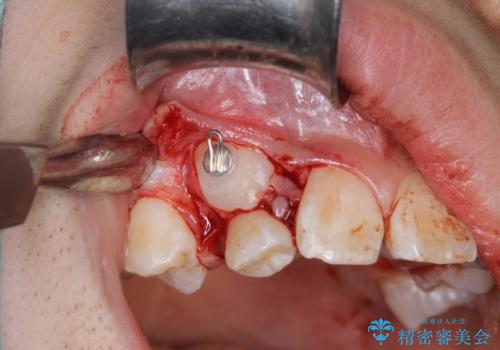

過剰歯と乳歯を抜歯後、リンガルアーチを用いて大まかな移動を行った後、マルチブラケットへ移行し、可及的に正常咬合へと誘導することを試みた。

乳歯・過剰歯を除去し、リンガルアーチを用いて埋伏していた犬歯を牽引、その他おおまかな動きを行った後、マルチブラケットにて永久歯の咬合を誘導しました。